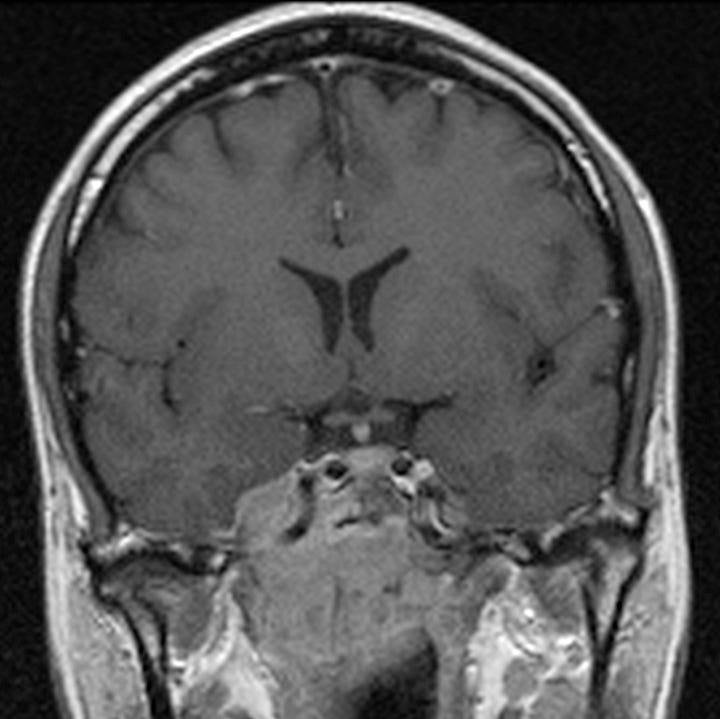

Nasopharyngeal carcinoma. A right sided soft tissue mass has eroded the petrous apex, right lateral clivus, and right lateral sphenoid sinus. Coronal postgadolinium T1-weighted image shows the large, enhancing right nasopharyngeal mass invading the clivus and right cavernous sinus and encasing the right cavernous internal carotid artery.